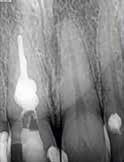

2. ábra: Kiindulási állapot.

3. ábra: A gyökértömés elkészítése során készített felvétel.

4. a–b. ábra: A reszorbciós üreg Biodentine-nel való feltöltése. Intraoperatív (a) és radiológiai felvétel (b). – 5. ábra: Az öt hónappal később látható állapot. Nem észlelhetők gyulladás fennállására utaló jelek.

A kezelés befejezését követően 30 hónappal készített CBCT-felvételen a gyógyulás jelei észlelhetők.

Az elváltozást egy diagnosztikai céllal készített panoráma-röntgenfelvételen észlelték. Az elváltozás kiterjedésének pontos meghatározása, valamint a kezelési terv felállításának és a várható prognózis megítélésének elősegítése érdekében CBCT-felvétel készült (1. a–c ábra). A reszorbtív lézió a fog gyökerének középső harmadában helyezkedett el és a

gyökér meziális felszínét perforálta. A lézió kerek és szimmetrikus volt, amely gyulladásos típusra utalt. Az oszteolitikus terület fókusza a perforáció közelében helyezkedett el (2. ábra). A csontban lévő lézió és a gyökérperforáció az endodonciai kezelés sebészi kiegészítését tette szükségessé. Ennek megfelelően az egy ülésben történő gyökérkezelést követően

1. a–c ábra: Kiindulási CBCT-felvétel. Az axiális síkú metszeten jól látható a gyökér falának perforációja (a); Koronális irányú metszet (b), Saggitális irányú metszet